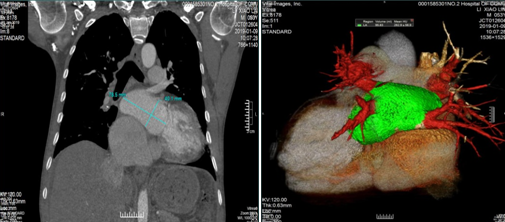

再发心律失常对于该患者来说无疑是一个噩耗,都说男人中年活得最辛苦,是爸妈的靠山,是家里的顶梁柱,是儿女生活的源泉。健康的身体最重要。患者听说,射频消融术能够根治房扑,改善房颤患者的生活质量,源于信任,遂前往心血管内科行房扑射频消融术。完善一系列术前检查后,医生们却犯难了,心脏彩超提示左房前后径49X36X68mm,右房横径64mm,LV:55mm;RV:34mm;EF:41%,肺血管螺旋CTV示:左心房左右径:86.8mm;前后径43mm,上下径:48mm。对于这么大的心房,有效标测是一大难点。

2019年1月11日,殷跃辉团队经过充分的术前准备,决定采用Rhythmia高精密度标测系统对患者实施射频消融手术。患者为巨大右心房,心脏明显转位,且曾因法洛四联症行外科手术,心脏结构异常复杂。虽经过了充分的困难准备,但手术一开始就遇到了困难,要进行复杂心律失常标测,冠状窦电极是必不可少的步骤,由于患者心脏结构复杂,右房巨大,经过反复尝试仍不能经股静脉途径将冠状窦电极置入冠状静脉窦,术中不得不临时改为经锁骨下途径放置冠状窦电极,经过约半小时的反复尝试方才将冠状窦电极成功放置到位。不过这仅仅是困难的开始,普通患者右房的标测是相对简单的,本中心已有上千例的经验,但该患者心房巨大,导管到位极其困难。此时Rhythmia Orion网篮电极的优势就体现出现来了,其电极较多,标测精度高,再经过耐心、仔细的标测后发现为三尖瓣峡部依赖性房扑,这时大家长舒了一口气,遂计划行三尖瓣峡部线性消融。不过,同样由于患者心房大,三尖瓣峡部异常长,导管不能良好的贴靠,肖培林博士不得不将消融导管拿出体外反复塑型,并在Lasso电极的辅助下完成了峡部消融,平时10分钟干完的事情,足足干了1小时。经过大家的努力最终患者房扑终止,转为窦性心律。术者肖培林博士感叹道:再也不要说典型房扑简单啦!